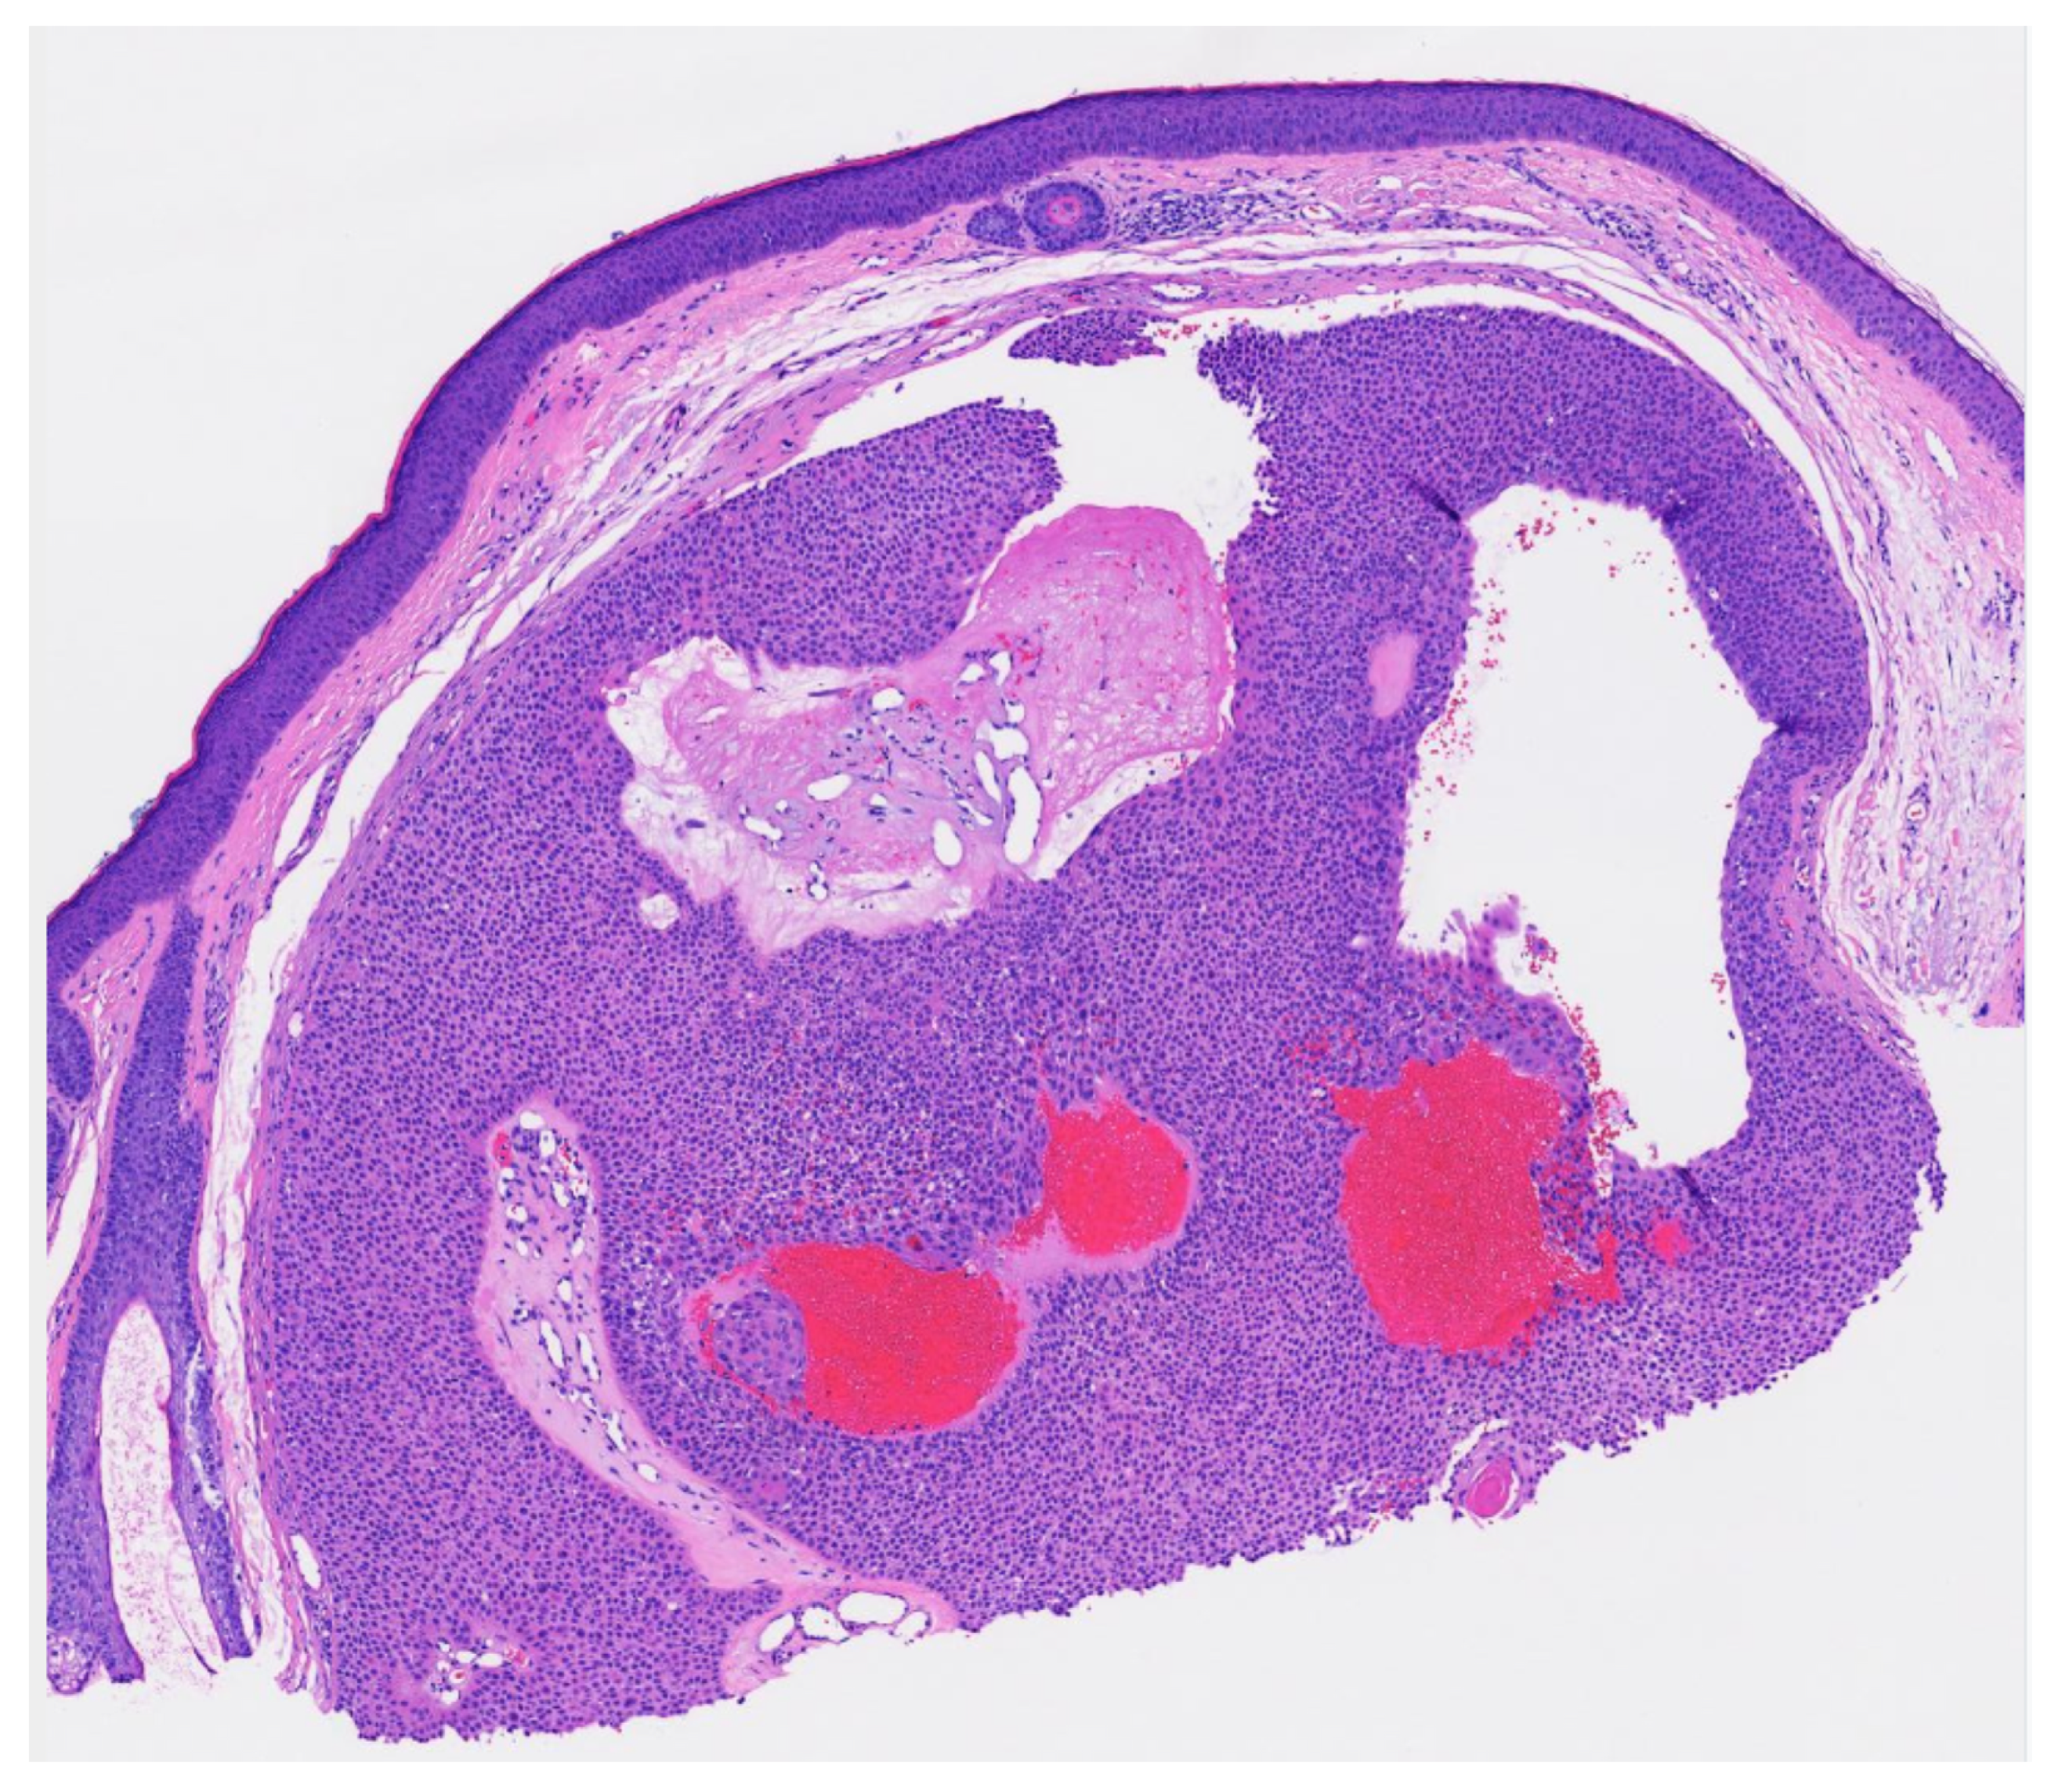

Poroma variants are differentiated based on the predominant cell type present and the degree of epidermal/dermal involvement [2]. However, multiple variants can exist within the same lesion. DDTs are primarily confined to the superficial dermis and are composed of small solid and cystic nodular aggregates of poroid, cuticular, and clear cells (Figure 3, Figure 4 and Figure 5) [2]. Eccrine poromas are also composed of all three cell types, but are primarily located in the epidermis and superficial dermis. Hidroacanthoma simplex is mainly composed of poroid cells, less cuticular cells, and no clear cells [2]. It is confined to the epidermis. Poroid hidradenoma contains a mixture of all three cell types and is also confined to the dermis [2]. In contrast to DDT, poroid hidradenomas have large aggregates of solid and cystic components and extend deeper into the reticular dermis and even subcutis [2].

The histopathologic diagnosis of DDT is rare due, in part, to the fact that some regard DDTs as poromas with a limited epidermal connection that has not been identified on the histologic sections examined or as hidradenomas that are smaller and more superficial [30]. As an example, Figure 3 may be regarded by some as representing a hidradenoma. This controversy in the histopathologic classification of poroid neoplasms without clear-cut evidence for the clinical significance of distinguishing these lesions from each other has given rise to the thinking that the poroma classification scheme may just be a matter of semantics [19]. This has led to some pathologists diagnosing these lesions under the overarching term as “acrospiroma” only without further classification.

Figure 3. Well circumscribed, dermal-based, solid and cystic tumor with no connection to the overlying epidermis (H & E, 2×).

Figure 5. Residual DDT on punch excision (from the transected spiecimen in Figure 3) (H & E, 10×).